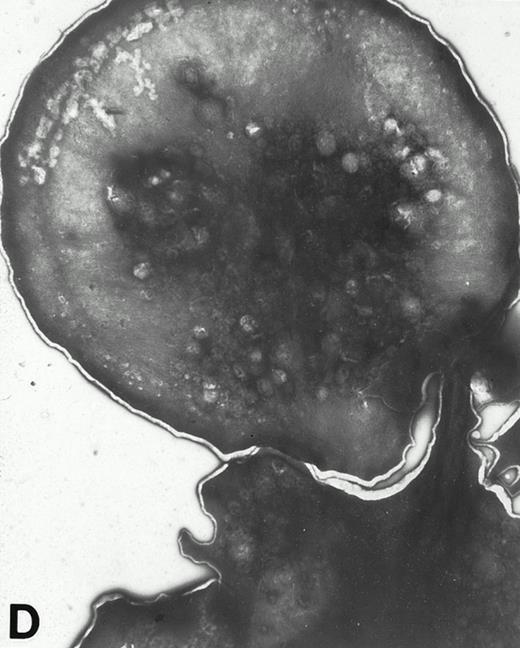

Wistar rat platelets allowed to adhere for 30 seconds (A) or 1 minute (B) onto Formvar-coated, carbon-stabilized grids, and subsequently fixed and stained with uranyl acetate. WF rat platelets allowed to adhere for 30 seconds (C) or 1 minute (D) onto Formvar-coated, carbon-stabilized grids. (A through D, original magnification ×3,700).

(A) Representative resting WF rat platelets prepared identically to resting Wistar platelets in Fig 2. (B through E) WF rat platelets allowed to adhere to Formvar-coated, carbon-stabilized grids from 30 seconds to 30 minutes, and subsequently fixed and stained with uranyl acetate. (B through E) illustrate the forms characteristic of WF rat platelet spreading, including platelets with stubby filopodia (B), lamellipodia (C), or fully spread forms (D and E). (E) shows the spread margin of a WF platelet at higher power. The arrowheads indicate microtubules and the asterisk shows the dense peripheral weave at the platelet margin. (B) 30-second adherent sample, (C) 1-minute adherent sample, (D and E) 30-minute adherent sample. (A through D, original magnification ×7,000; E, original magnification ×19,000).

In contrast, only a small percentage of adherent WF rat platelets were spindle shaped or spread with long filopodia after 30 seconds to 5 minutes. The majority of adhered WF platelets were round (with or without stubby filopodia) or spread with lamellipodia. From 10 to 30 minutes, the predominant forms were spread with lamellipodia and fully spread WF platelets (Figs 2 and 4).